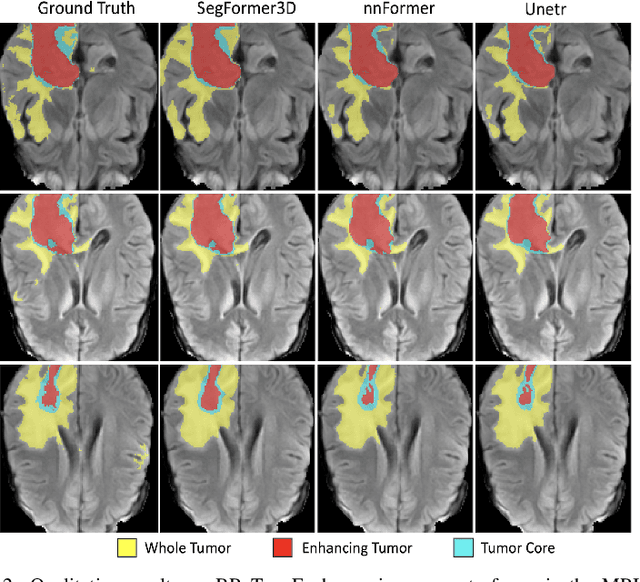

Abstract:The adoption of Vision Transformers (ViTs) based architectures represents a significant advancement in 3D Medical Image (MI) segmentation, surpassing traditional Convolutional Neural Network (CNN) models by enhancing global contextual understanding. While this paradigm shift has significantly enhanced 3D segmentation performance, state-of-the-art architectures require extremely large and complex architectures with large scale computing resources for training and deployment. Furthermore, in the context of limited datasets, often encountered in medical imaging, larger models can present hurdles in both model generalization and convergence. In response to these challenges and to demonstrate that lightweight models are a valuable area of research in 3D medical imaging, we present SegFormer3D, a hierarchical Transformer that calculates attention across multiscale volumetric features. Additionally, SegFormer3D avoids complex decoders and uses an all-MLP decoder to aggregate local and global attention features to produce highly accurate segmentation masks. The proposed memory efficient Transformer preserves the performance characteristics of a significantly larger model in a compact design. SegFormer3D democratizes deep learning for 3D medical image segmentation by offering a model with 33x less parameters and a 13x reduction in GFLOPS compared to the current state-of-the-art (SOTA). We benchmark SegFormer3D against the current SOTA models on three widely used datasets Synapse, BRaTs, and ACDC, achieving competitive results. Code: https://github.com/OSUPCVLab/SegFormer3D.git